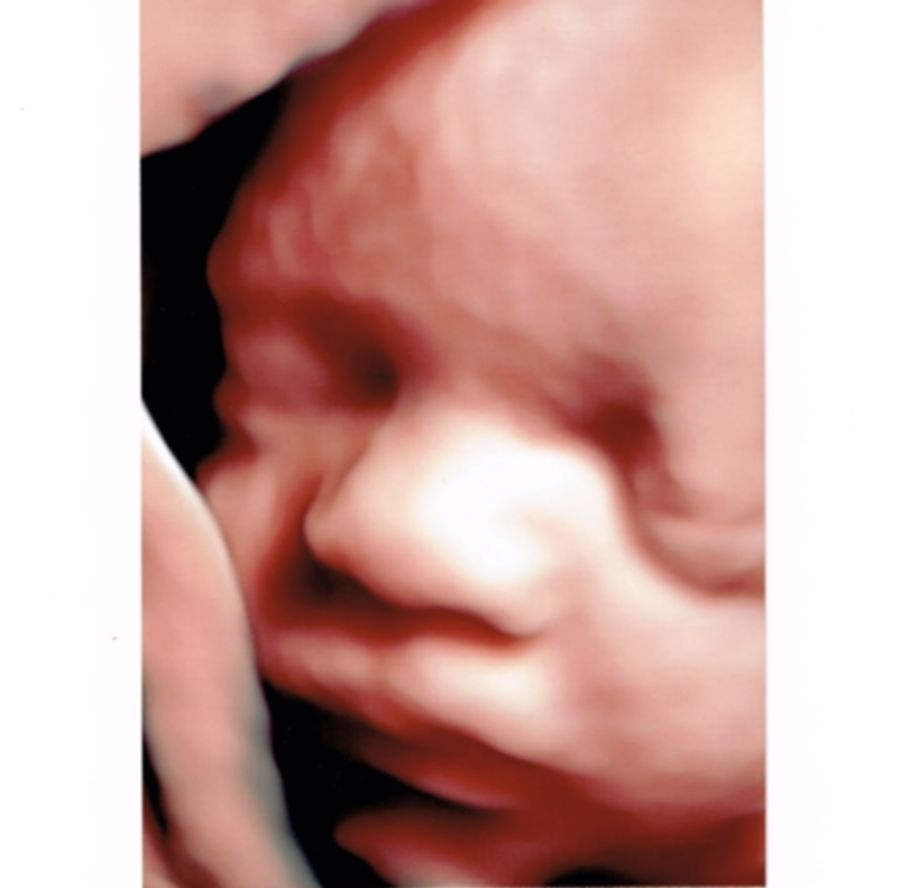

Moją pasją jest diagnostyka ultrasonograficzna w ginekologii i położnictwie, ocena anatomii płodu w badaniach prenatalnych. Nieustająco podnoszę kwalifikacje celem zapewnienia pacjentowi najlepszej opieki. Posiadam certyfikaty Polskiego Towarzystwa Ginekologów i Położników, Polskiego Towarzystwa Ultrasonografii oraz Fetal Medicine Foundation do wykonywania badań ultrasonograficznych.